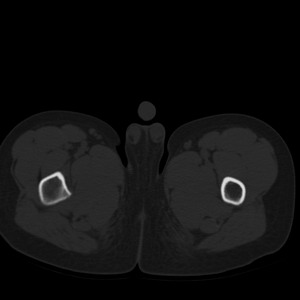

标题: PED1884:患者,男性,7岁。因右髋疼痛5天,而来院检查。 [打印本页]

标题: PED1884:患者,男性,7岁。因右髋疼痛5天,而来院检查。

因右髋疼痛5天,而来院检查。

我们考虑:1、骨皮质增厚症。2、畸形性骨炎。3、骨纤。

右髋疼痛,左侧病变,看来无症状。

支持左股骨上段骨纤维异常增殖症可能性大.